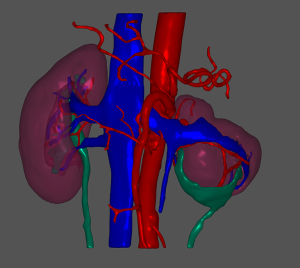

A 45-year-old woman was admitted to hospital complaining of a 1-month history of dizziness, and a transient ischemic attack was diagnosed. During a lung examination, her left kidney was found to be abnormal. The patient was not known to have kidney abnormalities, and there was no genetic history of this condition in her family. The patient did not present clinical symptoms of low back pain, hematuria, or urinary tract infection, and laboratory tests of renal function and urine routine were within normal ranges. The patient had no history of hypertension. A CT plain scan showed abnormalities in the left renal artery, vein, and ureter, and a reversed renal parenchyma with the collecting system protruding, while the right kidney was completely normal. Enhanced CT suggested that there was an artery in the left kidney, which entered the renal parenchyma in a mesh shape. There were 2 primary thick branches of deep veins, which merged with the reproductive vein at the renal pedicle and then merged into the inferior vena cava. The renal parenchyma was in a state of eversion and folding, and the renal papilla was prominent. Each renal papilla corresponded to a renal calyx, which converged into the renal pelvis on the ventral side (Figures 1,2). Using a software application (Mimics Innovation Suite 19.0, Materialise, Leuven, Belgium), we created a 3D reconstruction of the patient’s kidneys. The 3D-reconstructed images (Figures 3,4) showed that the right kidney was normal in anatomy and that the left kidney was abnormal. In Figures 3,4, it can be seen more intuitively and clearly that the left kidney has poor rotation, irregular physical contours, and an uneven surface; the renal pelvis and ureter are distributed in a “Y” shape. The final clinical diagnosis was CAKUT, and the patient’s clinical symptoms disappeared after conservative treatment. As the patient had no urinary system discomfort and her physical and laboratory examinations were normal, we prescribed a dynamic observation treatment plan with annual renal function and urinary system USs.